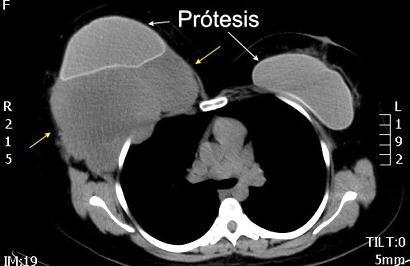

Prótesis

Sombra “simétrica y de densidad “uniforme” de las mamas

Prótesis de ambas mamas densamente calcificadas